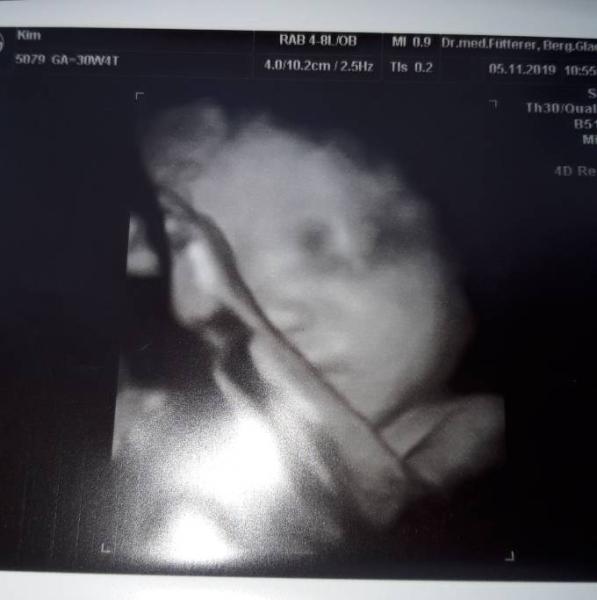

So ihr lieben nun war ich auch endlich beim 3ten Screening bei 30+4 (31 W) Die kleine Maus ist ca. 36cm lang und 1531g schwer, also eher eine kleine zierliche. Leider ist mein Eiweiß Gehalt erhöht ich soll noch mehr trinken und jeglichen Stress vermeiden. Zusätzlich kam bei der Untersuchung heraus das sie schon recht tief im Becken liegt und der Muttermund weich ist. Das mir jetzt ein absolutes Berufsverbot erteilt worden ist. Ich soll mich schonen und muss 3 mal am Tag Magnesium nehmen. Und muss jede Woche zur kontrolle. CTG war aber noch unauffällig. Sonst ist aber soweit alles zeitgerecht entwickelt und uns beiden geht es gut. Ein süßes Foto haben wir auch noch bekommen

Bild zu 3tes Screening heute - Forum für Januar - Mamis